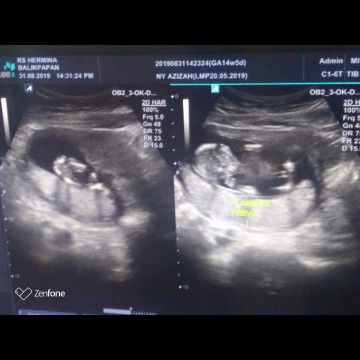

Plasenta Previa

Hai bunda semua, mau nnya sabtu kmrn saya cek kandungan di uk 14w5d kmdn dicek katanya saya plasenta previa... Sebelumnya saya cek didokter yang sama dokternya blg anak saya ga ada plasentanya (imposible). Nah ada kah bunda yg mengalami hal yg sama dengan saya? Ktnya kl plasenta previa itu smpai pendarahan/flek smntara saya dr awal kehamilan tdk mengalami flek/pendarahan sm sekali... Apa yg hrs saya lakukan ya bun? Saya kok jadi worried... Krna dikehamilan ptama saya ga ada riwayat plasenta previa